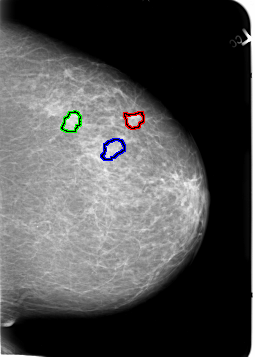

B_3021_1.RIGHT_MLO

FILE: B_3021_1.LEFT_MLO.OVERLAY

TOTAL_ABNORMALITIES 3

ABNORMALITY 1

LESION_TYPE MASS SHAPE LOBULATED MARGINS CIRCUMSCRIBED-ILL_DEFINED

ASSESSMENT 3

SUBTLETY 3

PATHOLOGY MALIGNANT

TOTAL_OUTLINES 1

BOUNDARY

ABNORMALITY 2

ABNORMALITY 3